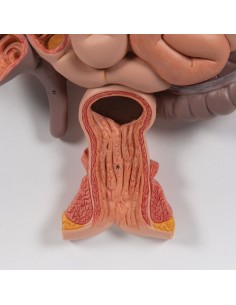

3B Scientific, modello anatomico funzionale di laringe: W42503